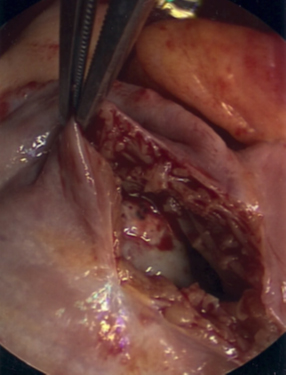

In the operating room, the patient underwent general endotracheal anesthesia. After his sternum had been divided, his right atrium and ventricle appeared distended, and there was evidence of moderate right ventricle dysfunction. On palpation of the right atrium and ventricle, the mass could be easily felt. After Heparin administration, the aorta was cannulated and there was bicaval venous cannulation. The heart was arrested and a right atriotomy was performed. The mass was stuck to the right atrium (Figure 2A and Figure 2B), tricuspid valve, and right ventricle. There was also invasion into the myocardium of the right ventricle. There was no possibility of excision of the mass in its entirety, but multiple biopsies were sent for evaluation (Figure 3). The frozen section returned as lymphoma.